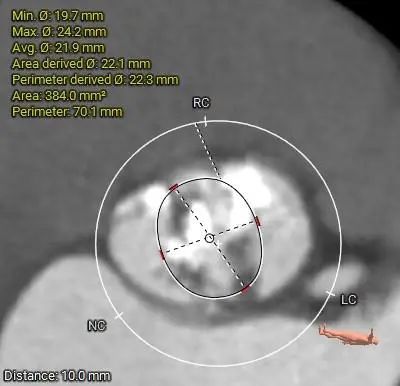

ANNULUS

2mm SUPRA ANNULUS